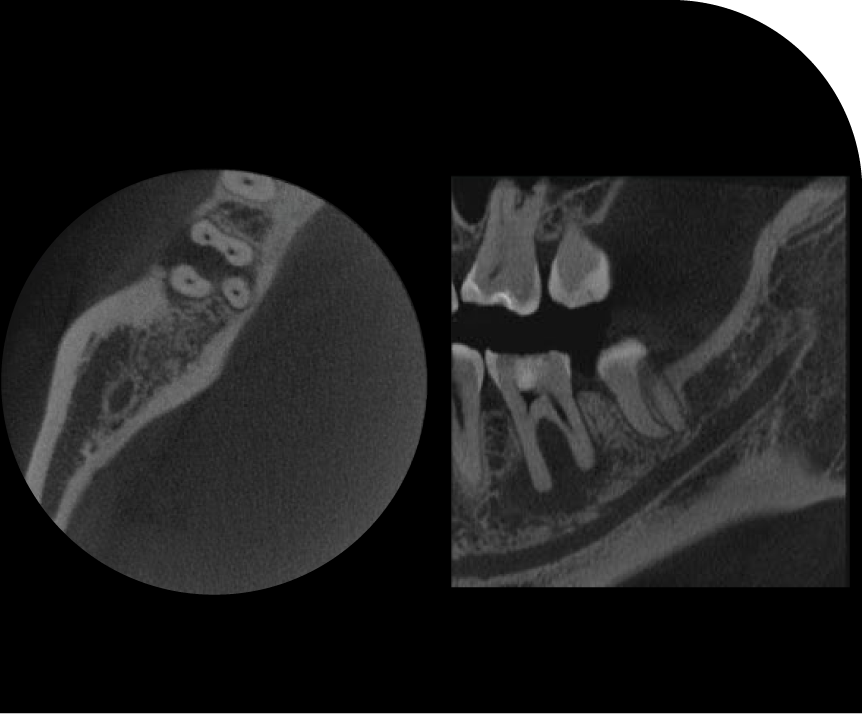

ENDO

Advanced Endodontic Solutions

Provide your patients with top-tier endodontic care through our specialised services. Our advanced endodontic solutions, including state-of-the-art imaging and precision treatment techniques, ensure accurate diagnosis and effective management of root canal issues. Enhance your practice with our expert support, delivering optimal outcomes and patient satisfaction in endodontic treatment.